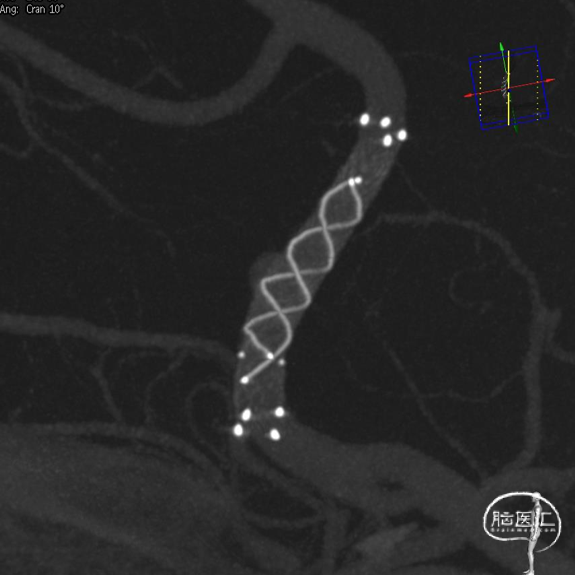

跨弓角度大,可见赛诺神畅 6F-105 APEX TRA®经桡远端通路导引导管柔软段跨越转弯处后沿泥鳅导丝一次顺利到达岩骨段。

选取良好工作角度。

导管顺利到位。

释放支架头端锚定,整个系统释放过程中稳定无明显跳跃。

造影定位,可见支架有效段位于远端瘤颈边缘。予以回收支架重新释放,回收过程通路系统支撑良好,支架导管顺利再次到位。

重新释放支架头端锚定,造影定位见有效段完全覆盖瘤颈。释放至转角处支架展开不佳,予以系统整体推挤后完全打开;支架完全释放后,支架导管在稳定有力支撑下顺利跨越支架。

术后3D造影及支架重建,可见支架展开和贴壁良好。